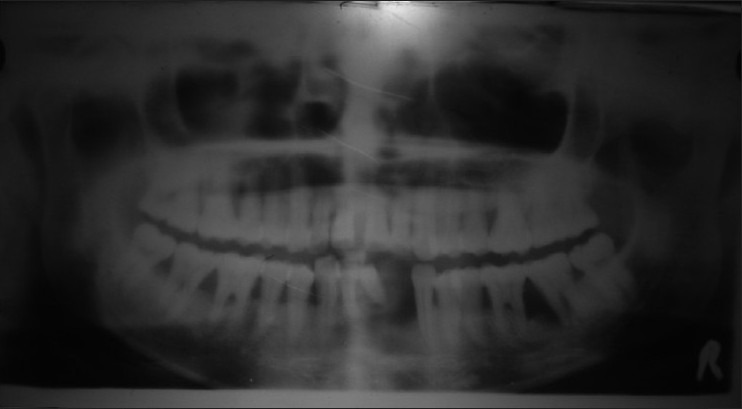

Hematological investigations revealed leucocytosis (TLC 12,300/mm3) and neutrophilia (absolute neutrophil count: 8,500/mm3). Biochemical profile including liver function tests and lipid profile were within normal limits. Bacterial cultures of the samples taken from subgingival pockets were positive for Actinobacillus actinomycetocomitans, Porphyromonas gingivalis and Escherichia coli. Histopathological examination of the skin over palmar surface revealed parakeratotic hyperkeratosis, hypergranulosis, regular acanthosis, and a dense perivascular lymphohistiocytic infiltrate. Orthopentomogram (OPG) revealed floating-in-air appearance with generalized horizontal bone loss up to middle-third of the roots of all teeth and vertical bone loss up to apical one-third of upper left 2nd premolar, lower right 1st and 2nd molars [Figure 4]. X-ray of hands and feet showed partial resorption of terminal phalanges and periarticular osteopenia with soft tissue swelling whereas, X-ray skull revealed no calcification. Ultrasound of abdomen was normal. Audiometric examination was within normal limits.

Figure 4.

OPG of PLS patient showing dental abnormalities with characteristic ‘floating- in- air appearance’

The diagnosis of PLS was made in our patient based on the presence of characteristic clinical and radiological features. She had typical PPK with transgradiens, periodontitis with loss of permanent incisor teeth, marked mobility and extensive alveolar bone loss giving the teeth a ′floating-in-air′ appearance on OPG. PPK is a feature of several heterogenous group of diseases: however, the association of PPK and premature periodontitis occurs only in PLS and Haim Munk syndrome . Both these entities can be distinguished based on the fact that a number of additional findings occur in HMS like onychogryphosis, arachnodactyly, acral osteolysis and pes planus, etc.[3]

Lack of phenotypic expression of the disease in her consanguineous parents and a family history of similar problem in her elder sister confers an autosomal recessive pattern of inheritance in our patient. Recent studies on PLS patients mapped the major gene locus on chromosome 11q 14 with mutation of the Cathepsin C gene[5] .The exact mechanism of the periodontal disease and increased susceptibility to infections in PLS patients is not clear, but it is attributed to the dysfunction in neutrophil motility to bacterial infection. Studies have pointed out an immunologically mediated gingival cementoblast disruption and recurrent gingival infections with organisms like A. actinomycetocomitans, Fusobacterium nucleatum, and Bacteroides gracilis as the cause of periodontitis.[6] Similar organisms were isolated in our patient associated chronic periodontitis resulting in loss of alveolar bone and shedding of teeth responsible for ‘floating-in-air’ appearance on OPG. Recurrent pyogenic infections skin and liver abscess are recognized in PLS;[7] however, this feature was not seen our patient.